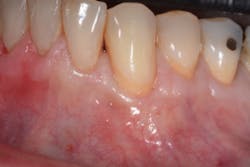

At least 2 mm of gingiva must be left on each side of the flap to preserve blood supply and avoid loss of crestal marginal bone. Although this technique is most effective in treating Miller Class I and II recession defects (figures 1 and 1a), it can be used to obtain partial root coverage around Miller Class III defects. This technique is best used around canines, premolars, and molars.

The Bernotti V-Y Flap involves making a submarginal supraperiosteal V-shaped incision 1 mm to 2 mm apical to the mucogingival junction, creating a pedicle flap (figures 2 and 2a). This flap is extended one tooth mesially and distally to the recession defect. It is important to note that the flap should leave the adjacent papillae intact in order to preserve blood supply. An intrasulcular incision is then made with a microsurgical blade to allow for coronal movement of the marginal tissue without tension (figure 3). The root is then scaled/root planed and chemically modified with an amoxicillin slurry for three minutes (figure 3a).